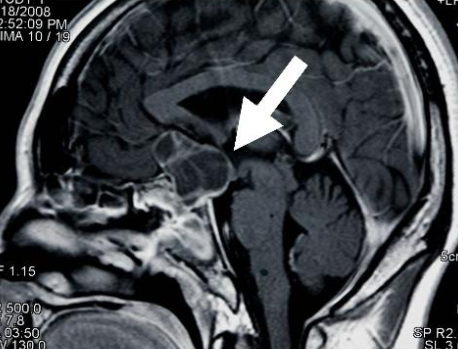

Nana,今年10岁,但是已经看不见这个国际了。那是2014年12月,在几周的时间里,她的视力迅速恶化。她在家里附近的医院接受了核磁共振检查,结果显示肿...

6岁儿童长期无精打采,竟是肿瘤所致 小金(化名)6岁时,开始间断性的出现无力、厌食情况,跟小朋友们一起玩的时候也无精打采。家长以为是孩子有情绪...

颅咽管瘤好发于成人及儿童两个高峰期,儿童多出现视力下降,由于儿童不会表述,所以难以发现,发现后肿瘤已经很大了。对于成人,肿瘤导致头痛,甚...